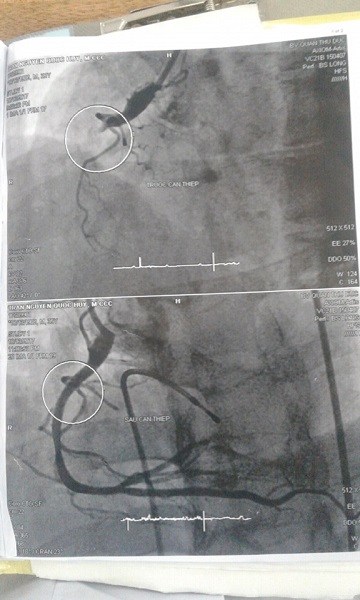

Hình ảnh trước và sau thông mạch máu. Ảnh: BVTĐ |

Kỳ tích xuất hiện, nhịp tim của bệnh nhân bắt đầu đập trở lại. Ê kip tái thông mạch máu tắc nghẽn. Sau gần một giờ thông tim, mạch máu bị tắc của bệnh nhân đã thông trở lại. Bệnh nhân được chuyển đến khoa Hồi sức để tiếp tục theo dõi, điều trị.